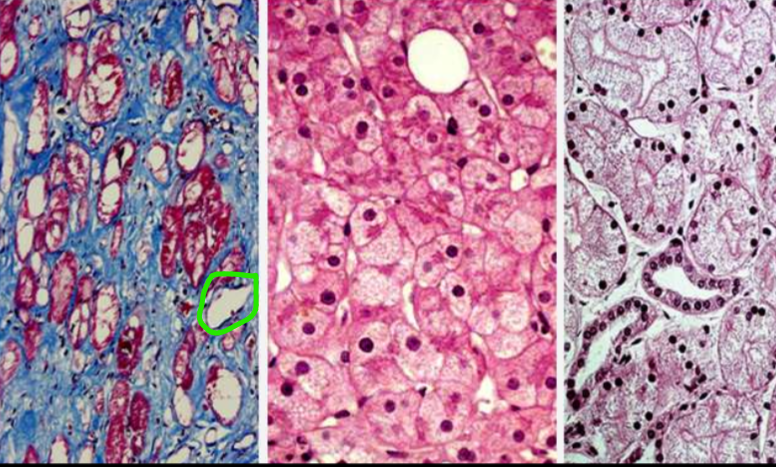

kas yra suriebėjimas

patologinis neutraliųjų riebalų kaupimasis ląstelėse

kaip dar vadinamas suriebėjimas

lipidoze

kur dažniausiai vyksta ląst. lipidozė

parenchiminėse ląstelėse: hepatociutose, rečiau kardiomiocituose, inksto epitleio

lipidozės/suriebėjimo morfologija

ląstelė padidėjusi

citoplazmoje baltai geltoni ląšeliai

išsaugo savo konfiguraciją

gali ląstelė atsistatyti

kas sąlygoja audinių suriebėjimą?

lėtinė hipoksija

intoksikacija (apsinuodijimas, taip pat ir alkoholiu)

koks svarbiausias ląstelių lipidozės mechanizmas

infiltracija